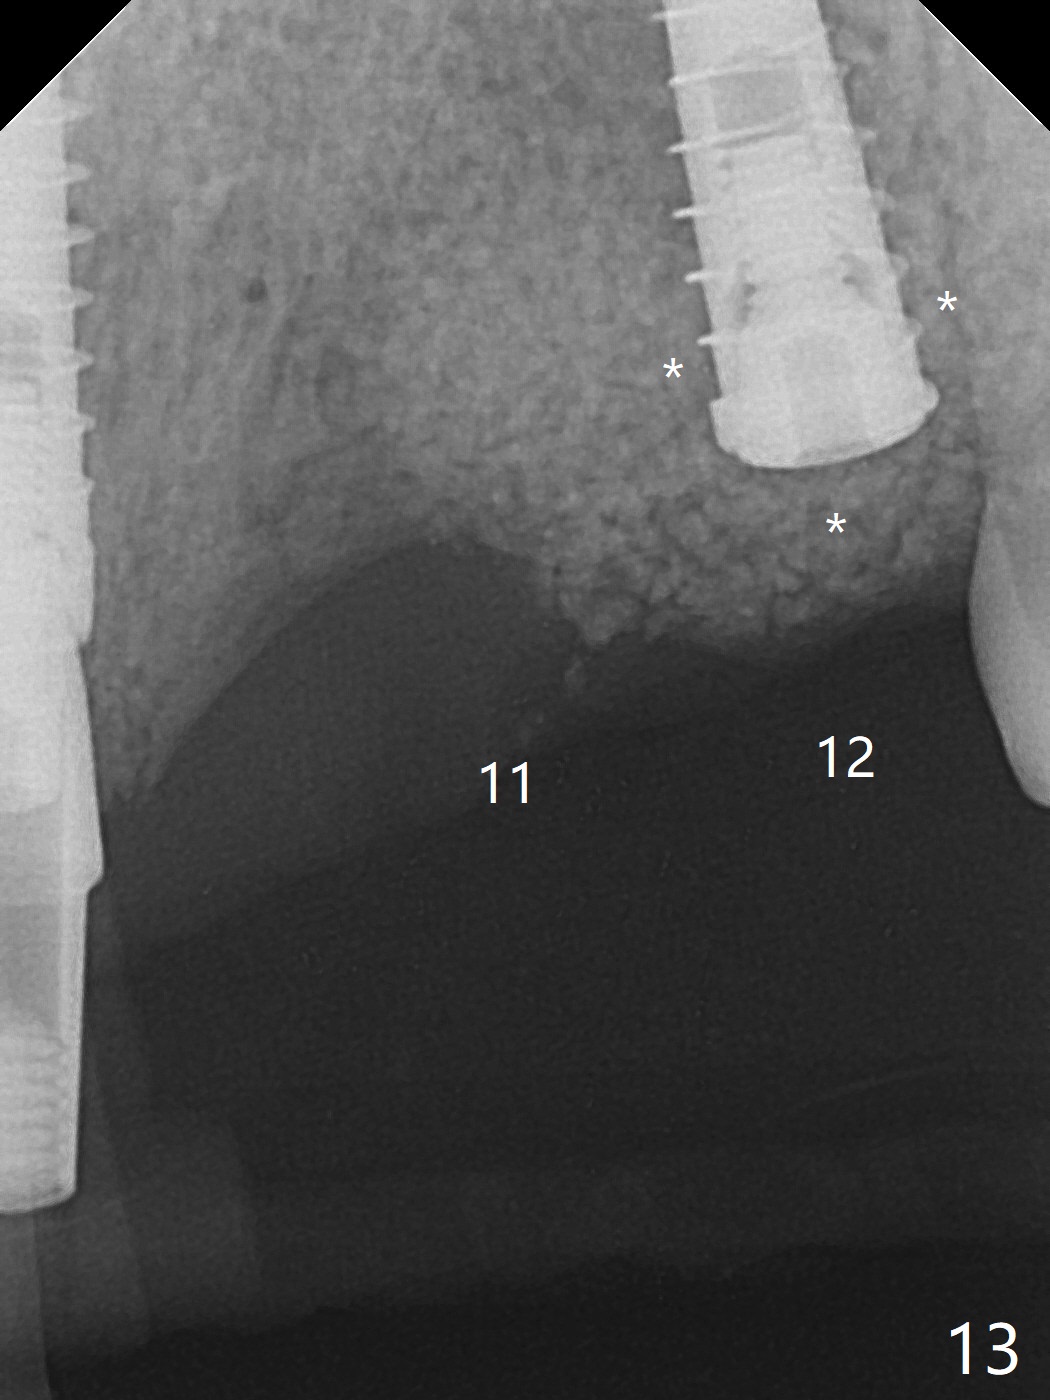

今天下午进入治疗室,粘性骨粉已制备:上清液来自红管(含促凝剂),离心3分钟(图一);再离心10分钟上清液就转变PRF,压制后,使用前剪成三块(图二:黑线),其中两块punch一个洞(图二:圆圈),插入7,9号牙基台固定;大块覆盖11/12号牙牙槽窝(图十四)。7,9,11,12号牙必须拔除(图三),然后在7,9,12种植。由于缺失左下磨牙,前牙垂直距离减少(图四)。完成9号牙位钻洞后,利用fixture mount(图五:M)植入植体,并留在原位固定导板(图六),然后7号牙种植,也留下fixture mount(图六:7,9),最后完成12号牙植入,但是后者扭力低,放置愈合螺帽(图九),而7,9号牙位放置修复基台(图七,八(使用5.5毫米profile drill后),好像基台没有完全就位。7号牙位更换基台似乎没帮助(图十),9号牙位再次放置同一个基台临床上仿佛有改变(比较图八与十二)。放置粘性骨粉后(图十一至十三),牙槽窝口覆盖PRF膜(图十四:P(A:基台)),最后使用树脂敷料固定骨粉和膜(图十五,六),基台帮助敷料固位,没有咬合干扰(图十七:*)。树脂敷料部分解决美观问题,一个月后撤除,如果植体仍有稳定性,可能制作7-10临时牙桥,可能部分维持或者恢复牙龈外形。术后一周病人主诉后面植牙和鼻底疼痛,11号牙根尖牙龈充血(图十八),轻度触痛,可能与术中尚未完全清创有关(图十九(术前CT 3D图像))。再服用Amoxicillin一周,症状好转,鼻底轻度触痛(图二十)。术后1.5月没有任何不适,撤除树脂敷料,7号牙基台(袖)显得太长,换一个短的(4.5x4(5)(图十,十一)->4x4(3)毫米)毫米),植骨好像愈合正常(图二十一:*)。7号牙换了短的基台,9号牙基台高度调整后,与对合牙有足够空间做临时牙桥,最好8,10号牙位牙龈应该凹陷(图二十二:*),有pontic外形。另外9号牙基台颊侧牙龈边缘有所修整,临时牙桥准备。先做7-10临时牙桥,理想临时牙桥pontic处树脂应该多些(图二十三:白线)压迫牙龈形成凹陷。11,12号牙牙槽窝在树脂(Bosworth)敷料下也正常愈合(图二十四)。